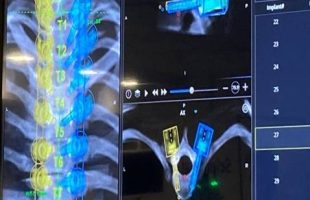

Η πάσχουσα, σε ηλικία 15 ½ χρονών, διαπιστώθηκε ότι παρουσιάζει σημαντικότατη παραμόρφωση της Σπονδυλικής Στήλης. O γενόμενος τότε ακτινολογικός έλεγχος αποκάλυψε την ύπαρξη Διπλού Οργανικού Σκολιωτικού Κυρτώματος της Σπονδυλικής Στήλης. Εικόνα 1 Προσθιοπισθία ακτινογραφία της Σπονδυλικής Στήλης σε ορθία στάση. Παρατηρείται η ύπαρξη (Δ) θωρακικού κυρτώματος (Θ3-Θ10) 66ο και (Αρ) θωρακο-οσφυϊκού κυρτώματος (Θ11-Ο4) 72Ο .